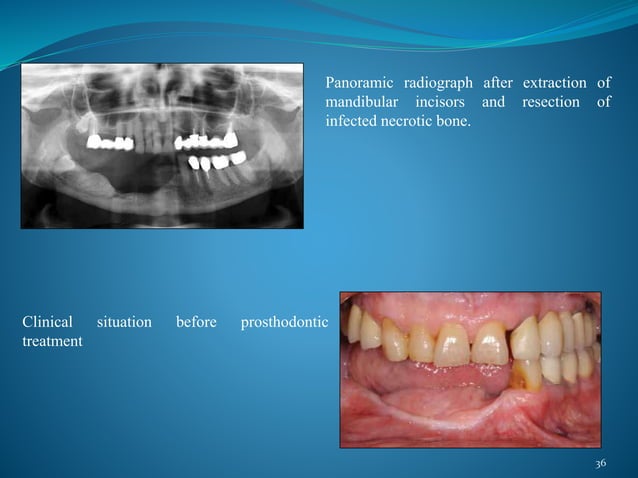

Clinical Characteristics Of An Allergic Reaction To A Polyether Dental

impression polyether allergic reaction mucosa preoperative

Clinical Characteristics Of An Allergic Reaction To A Polyether Dental

www.slideshare.net

www.slideshare.net

Clinical Characteristics Of An Allergic Reaction To A Polyether Dental

www.slideshare.net

www.slideshare.net

Clinical Characteristics Of An Allergic Reaction To A Polyether Dental

www.slideshare.net

www.slideshare.net

Clinical Characteristics Of An Allergic Reaction To A Polyether Denta…

www.slideshare.net

www.slideshare.net

allergic dental characteristics polyether clinical

Clinical Characteristics Of An Allergic Reaction To A Polyether Dental

www.slideshare.net

www.slideshare.net

Clinical characteristics of an allergic reaction to a polyether dental. Clinical characteristics of an allergic reaction to a polyether dental. Clinical characteristics of an allergic reaction to a polyether dental